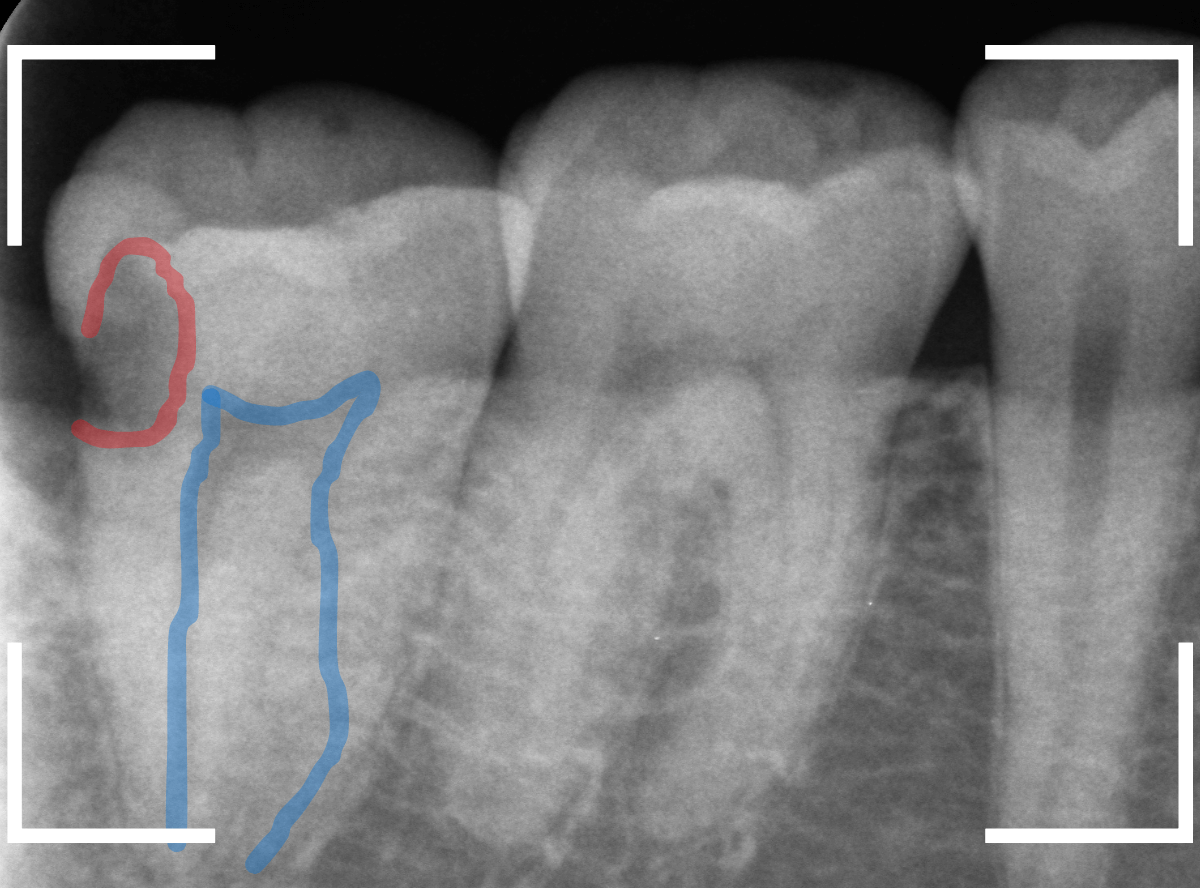

レントゲン写真です。

レジンの下が虫歯になっているのがわかります。

レントゲン写真で確認します。

青い線が歯の神経、赤い線が虫歯です。

おやしらずがあった際にはわかりづらかったですが、歯の後ろ側のおやしらずが重なっていたところが虫歯になっているのがわかります。

おやしらずが原因で、このように手前の歯が虫歯になってしまう事が多いために、抜歯を勧められる事が多いのです。

そして、虫歯の部分におやしらずが被さっていたために、しみる症状などを感じなかったのです。